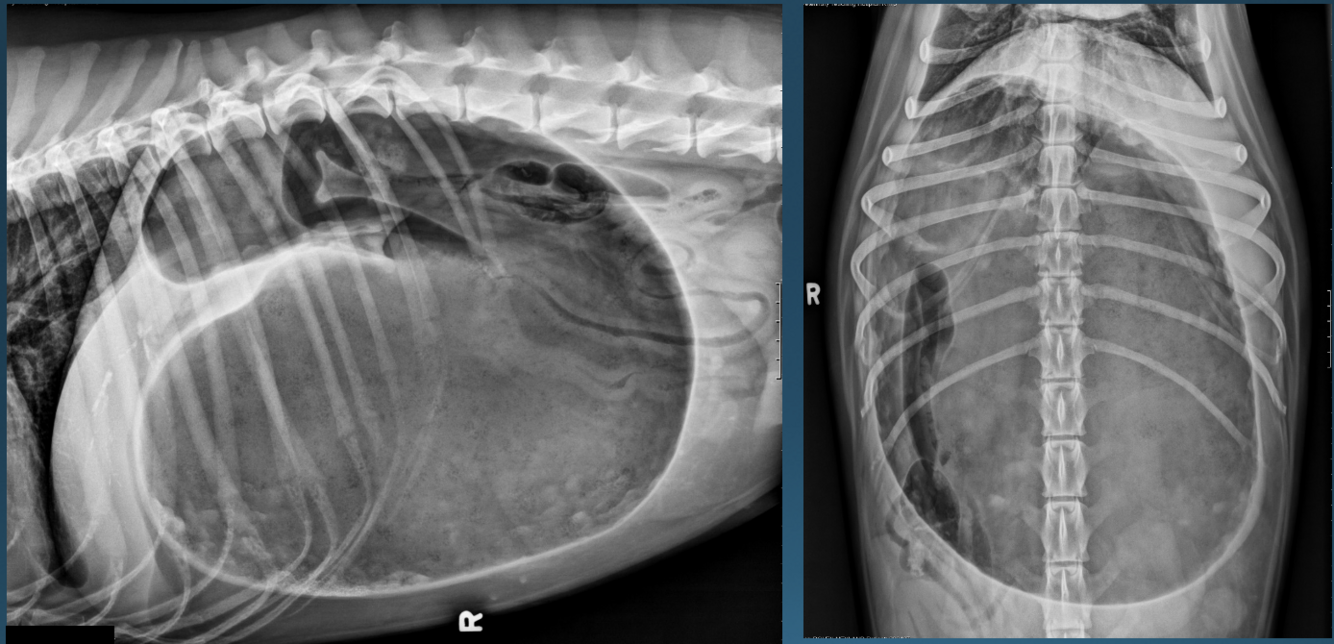

What is shown in this image?

hiatal hernia (feline)

What are the imaging findings in a hiatal hernia?

*caudal mediastinal structure in area of esophagus

-at margin of diaphragm

-soft tissue opacity +/- gas

*may appear continuous with the stomach

*may disappear if sliding